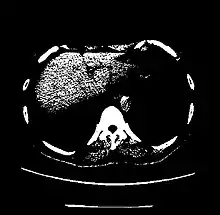

A practical application of this is in evaluation of tumors, where, for example, an adrenal tumor with a radiodensity of less than 10 HU is rather fatty in composition and almost certainly a benign adrenal adenoma.[28]

| Parenchyma | Lung | −700 to −600[22] |

| Kidney | +20 to +45[5] | |

| Liver | 60 ± 6[23] | |